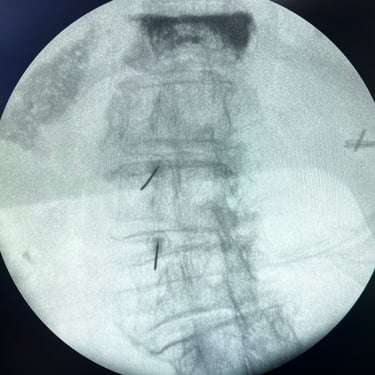

🧠 Infiltración Lumbar Selectiva | Espacio Foraminal Anterior, Articulaciones Facetarias y Ramos Mediales.

La infiltración lumbar selectiva permite tratar y diagnosticar el dolor lumbar mediante la aplicación dirigida de fármacos en el espacio foraminal anterior, las articulaciones facetarias y los ramos mediales. Este procedimiento reduce la inflamación, alivia la compresión nerviosa y brinda un control eficaz del dolor, favoreciendo una mejor calidad de vida.